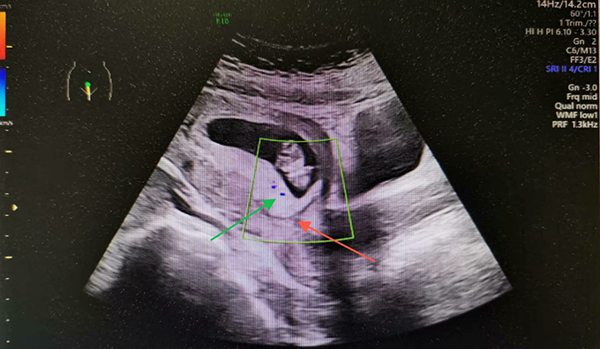

【学雷锋季】超声科系列科普 | 探秘胎盘…